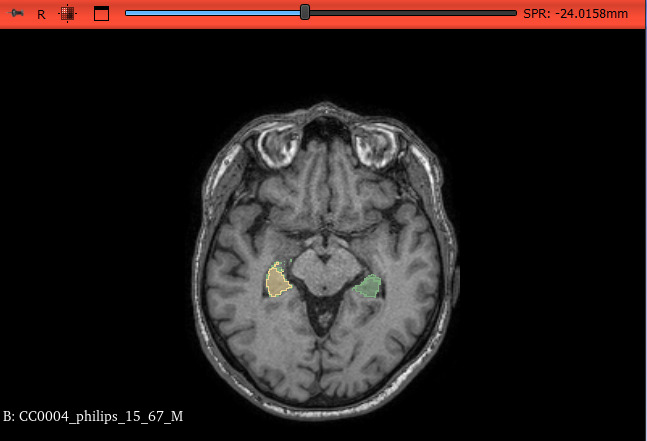

La segmentazione dell’ippocampo in risonanza magnetica (RM) è cruciale per l’analisi del sistema nervoso centrale, specie nello studio delle patologie neurodegenerative. L’uso di algoritmi di intelligenza artificiale (AI) consente di automatizzare il processo, migliorando rapidità, riproducibilità e standardizzazione, e riducendo la variabilità inter-operatore tipica delle tecniche manuali. In tale contesto, il tool Brain Parcellation di 3D Slicer rappresenta una soluzione promettente. Con questo studio si è andati a valutare le performance di un algoritmo AI in 3D Slicer, confrontandolo con segmentazioni manuali di riferimento per verificarne accuratezza e affidabilità in ambito clinico e di ricerca.

Sono stati analizzati 25 pazienti da un dataset open source con immagini RM encefaliche acquisite con protocolli standard e relative segmentazioni manuali dell’ippocampo. Le immagini sono state elaborate con il tool Brain Parcellation, che ha generato automaticamente le maschere dell’ippocampo, poi confrontate con segmentazioni manuali eseguite da neuroradiologi. Il tempo medio per ciascuna segmentazione automatica è stato di circa 12 minuti. La valutazione quantitativa è stata condotta con il modulo SlicerRT, tramite estrazione di Dice Similarity Coefficient (DSC), Hausdorff Distance (HD), volume della segmentazione automatica (Compare Volume) e volume manuale (Reference Volume), per analizzare sovrapposizione spaziale e coerenza volumetrica.

Il valore medio del DSC è risultato 0.79, indicando buona corrispondenza tra segmentazioni automatiche e manuali. Le misure di HD hanno confermato elevata similarità dei contorni, compatibile con la risoluzione dell’imaging e coerente con i valori di DSC. Le due metriche, valutando aspetti complementari, si bilanciano, rafforzando l’affidabilità dei risultati. I volumi ottenuti con il tool automatico sono risultati coerenti con quelli manuali, con differenze entro limiti clinicamente accettabili.